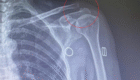

Trong vòng 1-2 ngày sau mổ, bệnh nhân sẽ được chụp X-quang hệ tiết niệu để kiểm tra tình trạng sót sỏi, kiểm tra xem sonde JJ có đúng vị trí không? Nếu đã sạch sỏi; sonde JJ đúng vị trí thì bệnh nhân có thể được rút ống dẫn lưu thận và ống tiểu. Ở vị trí dẫn lưu sau khi rút ống có thể xuất hiện tình trạng rỉ nước tiểu và sẽ chấm dứt sau 3 – 6 giờ nhờ băng ép. Nếu tình trạng này vẫn tiếp tục kéo dài cần báo ngay cho điều dưỡng.